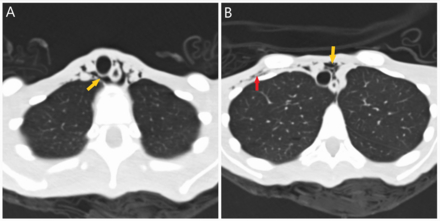

A 21-year-old female with depression presented with two days of sharp, positional chest pain, dyspnea, palpitations, and weakness. She reported eating less than one meal per day, running 22 miles daily, self-induced vomiting, and experiencing one year of amenorrhea. On exam, her BMI was 10.7 kg/m^2, with lanugo, proximal muscle weakness, and a pericardial friction rub. Labs showed hypokalemia, hypophosphatemia, transaminitis, elevated CK, and leukocytosis. ECG demonstrated diffuse ST elevations and PR depression in aVR. Transthoracic echocardiography revealed a moderate pericardial effusion without tamponade (Figure 1). CT chest showed pneumomediastinum and subcutaneous emphysema without evidence of esophageal perforation (Figure 2). Workup for infectious, autoimmune, ischemic, and thyroid causes was negative. She was diagnosed with severe AN and major depressive disorder. Management included IV fluids, electrolyte repletion, and nutritional support. Pericarditis was treated with ibuprofen and colchicine. Psychiatric therapy included olanzapine and mirtazapine for appetite stimulation and mood support. She was discharged to a structured inpatient nutritional rehabilitation program.

This is the first reported case of symptomatic pericarditis in AN. While pericardial effusions are often asymptomatic and linked to myocardial and pericardial fat loss, this case suggests purging-induced esophageal microperforations may cause subclinical mediastinitis, triggering pericardial inflammation. Cardiovascular complications occur in up to 87% of patients with AN. A high index of suspicion for pericarditis is warranted in malnourished patients presenting with chest pain. ECG, echocardiography, and imaging are essential.